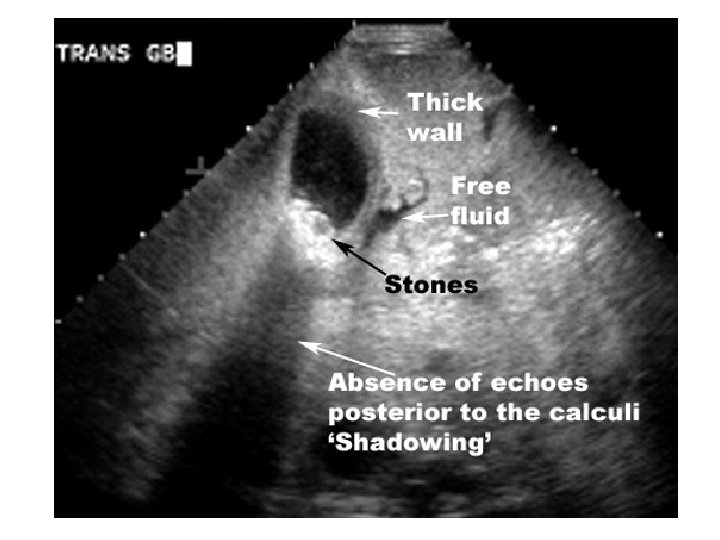

• DIAGNOSTIFIKIMI: USG abdominale= standarti i arte!!!!